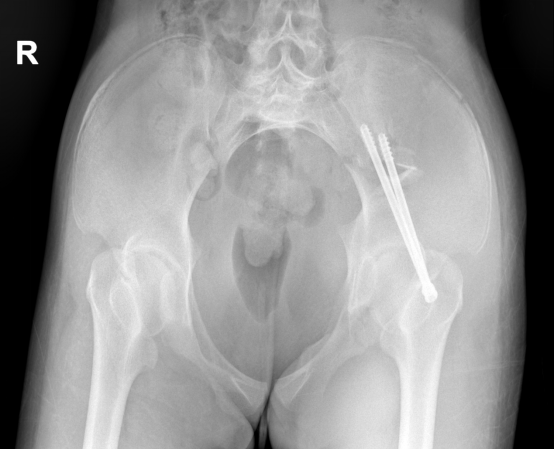

▲术前CT示骨盆骨折完整性被破坏

骨科主任张成勇、副主任许锦涛带领团队细心研判,考虑到患者全身多发骨折,其中骨盆(Tile B2.1型)、腰椎及左踝关节需手术治疗,征得患者家属知情同意后,先行骨盆骨折手术治疗。

▲术后X片